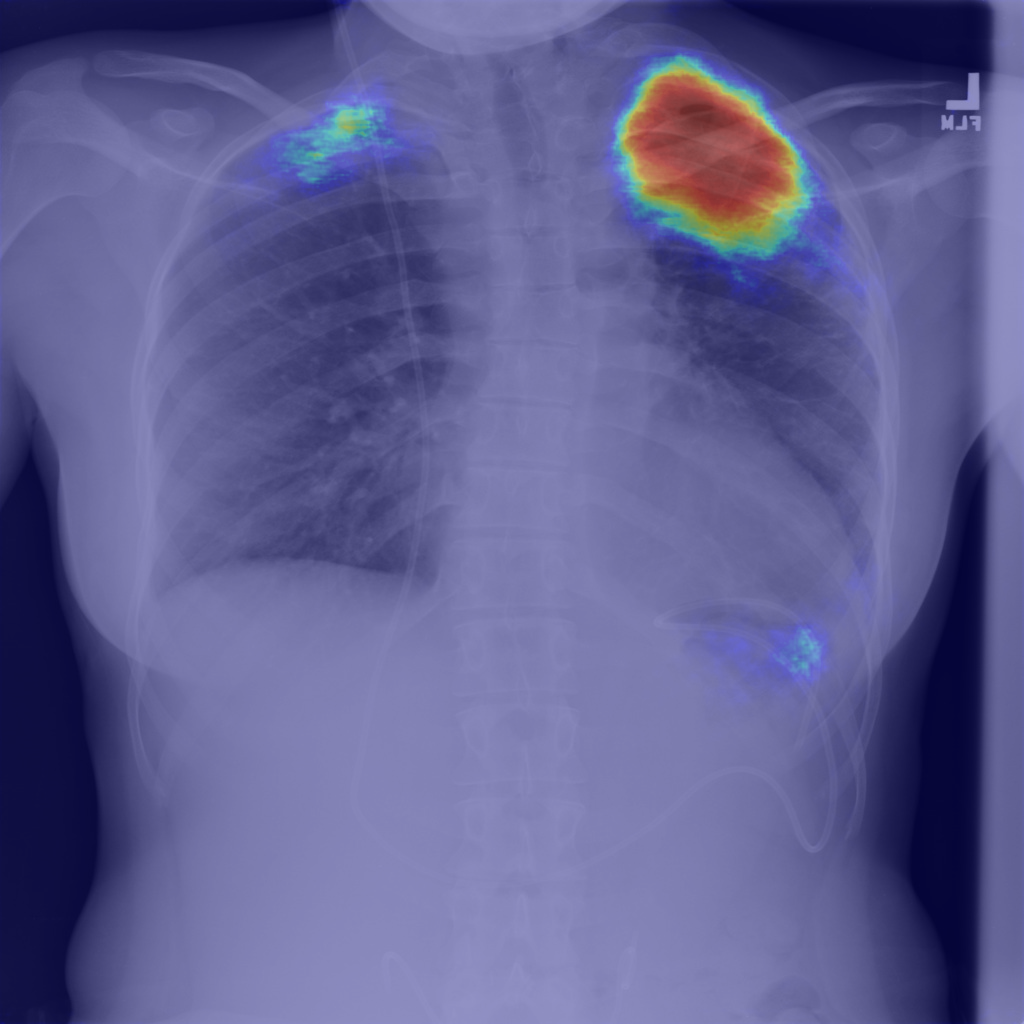

Refer to caption

(b) Step1.CAM

Figure 1: Pneumothorax localization maps for (a) a random image from the test set at each consecutive step of our method: (b) map after CAM extraction, (c) improved map by IRNet trained on the outcomed of step 1, (d) prediction of U-Net trained on step 2 results, all compared to (e) ground truth mask.

We present method’s explainability via disease localization regions; cf. Figure 1. We provide qualitative results of segmentation on validation images from both datasets in Figure 2 and Figure 3. We show the resulting maps at each step of our method; the figures demonstrate how the performance improves after each step. We achieve comparable results to state-of-the-art method on PASCAL VOC 2012; cf. Table 4.